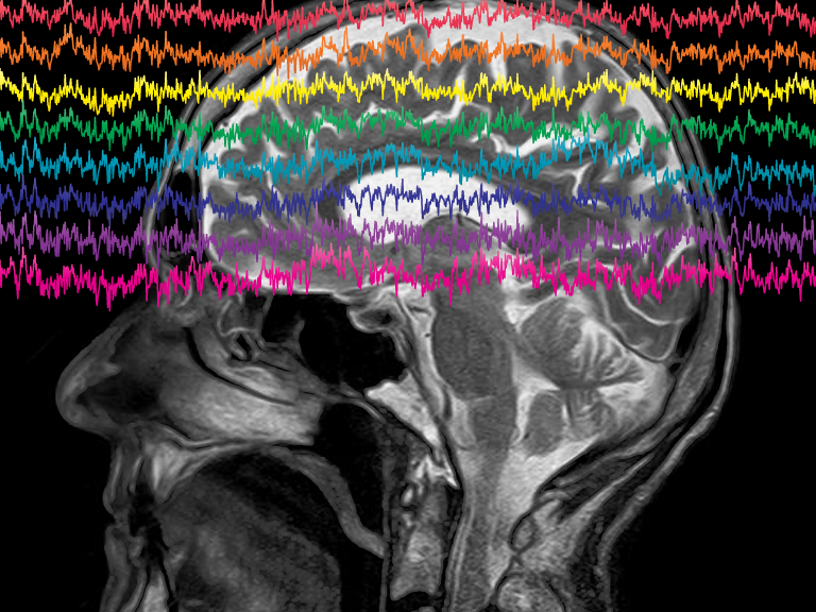

Глубокая стимуляция мозга (deep brain stimulation), при которой используется имплантат, посылающий электрические импульсы в определенную часть мозга, активно развивается в последние два десятилетия. Наибольших успехов этот метод достиг при лечении резистентной к лекарствам эпилепсии и симптомов болезни Паркинсона, где он помог уже тысячам пациентов. Также глубокая стимуляция мозга успешно применяется при дистонии, треморе и хронической боли. Устройство хирургическим путем помещается под кожу головы.

Испытание проводилось в течение полугода. Врачи наблюдали за двумя пациентами, у которых имплантированное устройство контролировало активность в области мозга, называемой прилежащим ядром. Прилежащее ядро участвует в формировании ощущений удовольствия. Оно служит частью «системы вознаграждения» мозга и связано с возникновением зависимостей. Всякий раз, когда устройство воспринимало определенный тип нейронной активности в прилежащем ядре, который, как было обнаружено в предыдущих исследованиях, предшествовал появлению тяги к еде, оно автоматически стимулировало эту область мозга, нарушая сигналы, связанные с тягой. За шесть месяцев лечения пациенты сообщали о гораздо меньшем количестве эпизодов переедания, а вес их снизился: каждый потерял более пяти килограммов.